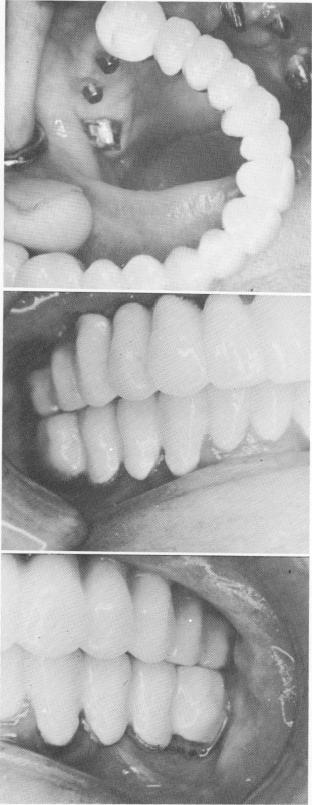

placed over the implant posts (Fig. 11-129). A wax interocclusal record of centric relation was made, followed by a full upper plaster index that included the gold and acrylic copings (Fig. 11-130). An alginate (irreversible hydrocolloid) impression of the teeth in the opposing dental arch was also taken.

At the next visit a one-piece metal casting, which included the six copings and all of the metal pontics, was fitted over the implant posts and tooth abutments (Fig. 11-131). All necessary gingival and occlusal adjustments were made. A final wax interocclusal record of centric relation was taken.

At this point if any discrepancy exists between the tissue-bearing surfaces of the pontics and the under-lying soft tissues, an Opotow* paste mix is placed over the shy surfaces of the pontics and the frame-

Fig. 11-133. The biscuit-baked prosthesis was tried. All necessary occlusal and esthetic changes were done during the final glazing process of the porcelain.

Fig. 11-134. The final prosthesis cemented in place.